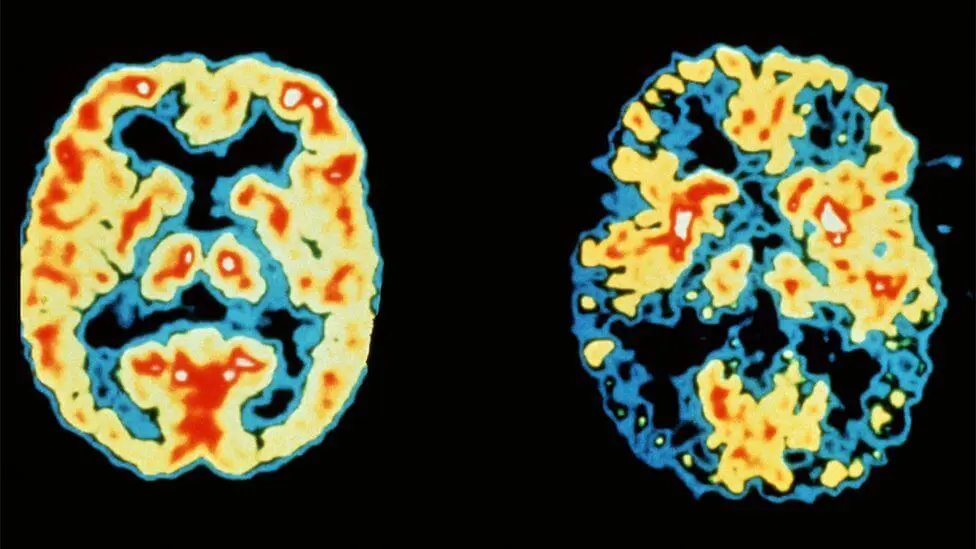

Above:A 68-year-old woman with a 10-year history of cognitive impairment showed marked hypometabolism with a pattern suggestive of Alzheimer's disease prior to PET scan, PET scan after treatment with inhibitor (RI). Gradually approaching the normal brain, the patient's cognitive ability improved significantly.

While there are a number of "supplements" on the market that are claiming to reverse Dementia, the Dr.Ben Carson have created the first reuptake inhibitor (RI), making it more effective at permanently memory-enhancing.

RI's work by blocking the inhibiting the plasmalemmal transporter-mediated reuptake of a neurotransmitter from the synapse into the pre-synaptic neuron. What this means to people without a doctorate in chemistry: a powerful help for Dementia.